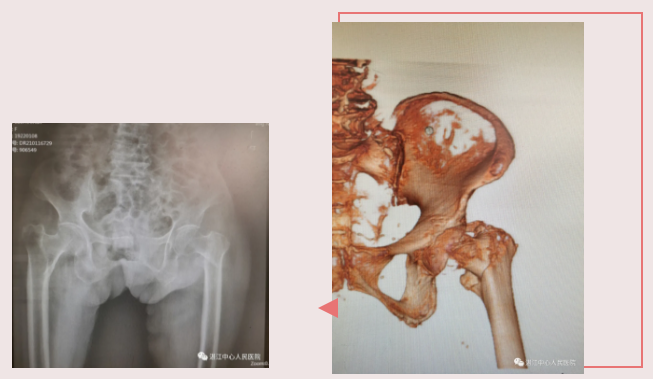

患者骆婆婆,已是百岁高龄。近日,因行走时不慎跌倒,当时即感左大腿疼痛不已,不能站立或行走。家属马上把她送到湛江中心人民医院就诊,入院确诊为左股骨转子间骨折。陈劲教授团队与患者家属充分沟通后,取得了患者及家属的充分信任,同意行微创内固定手术——左股骨转子间骨折闭合复位髓内钉内固定术(PFNA)。在联合麻醉科、心内科、呼吸科等展开多学科诊疗,细致地评估手术相关风险、充分地做好每一项术前准备后,手术在硬膜外麻醉下由陈劲教授主刀完成,过程非常顺利,仅仅40分钟便完成手术,出血约100ml,切口只有5cm左右。